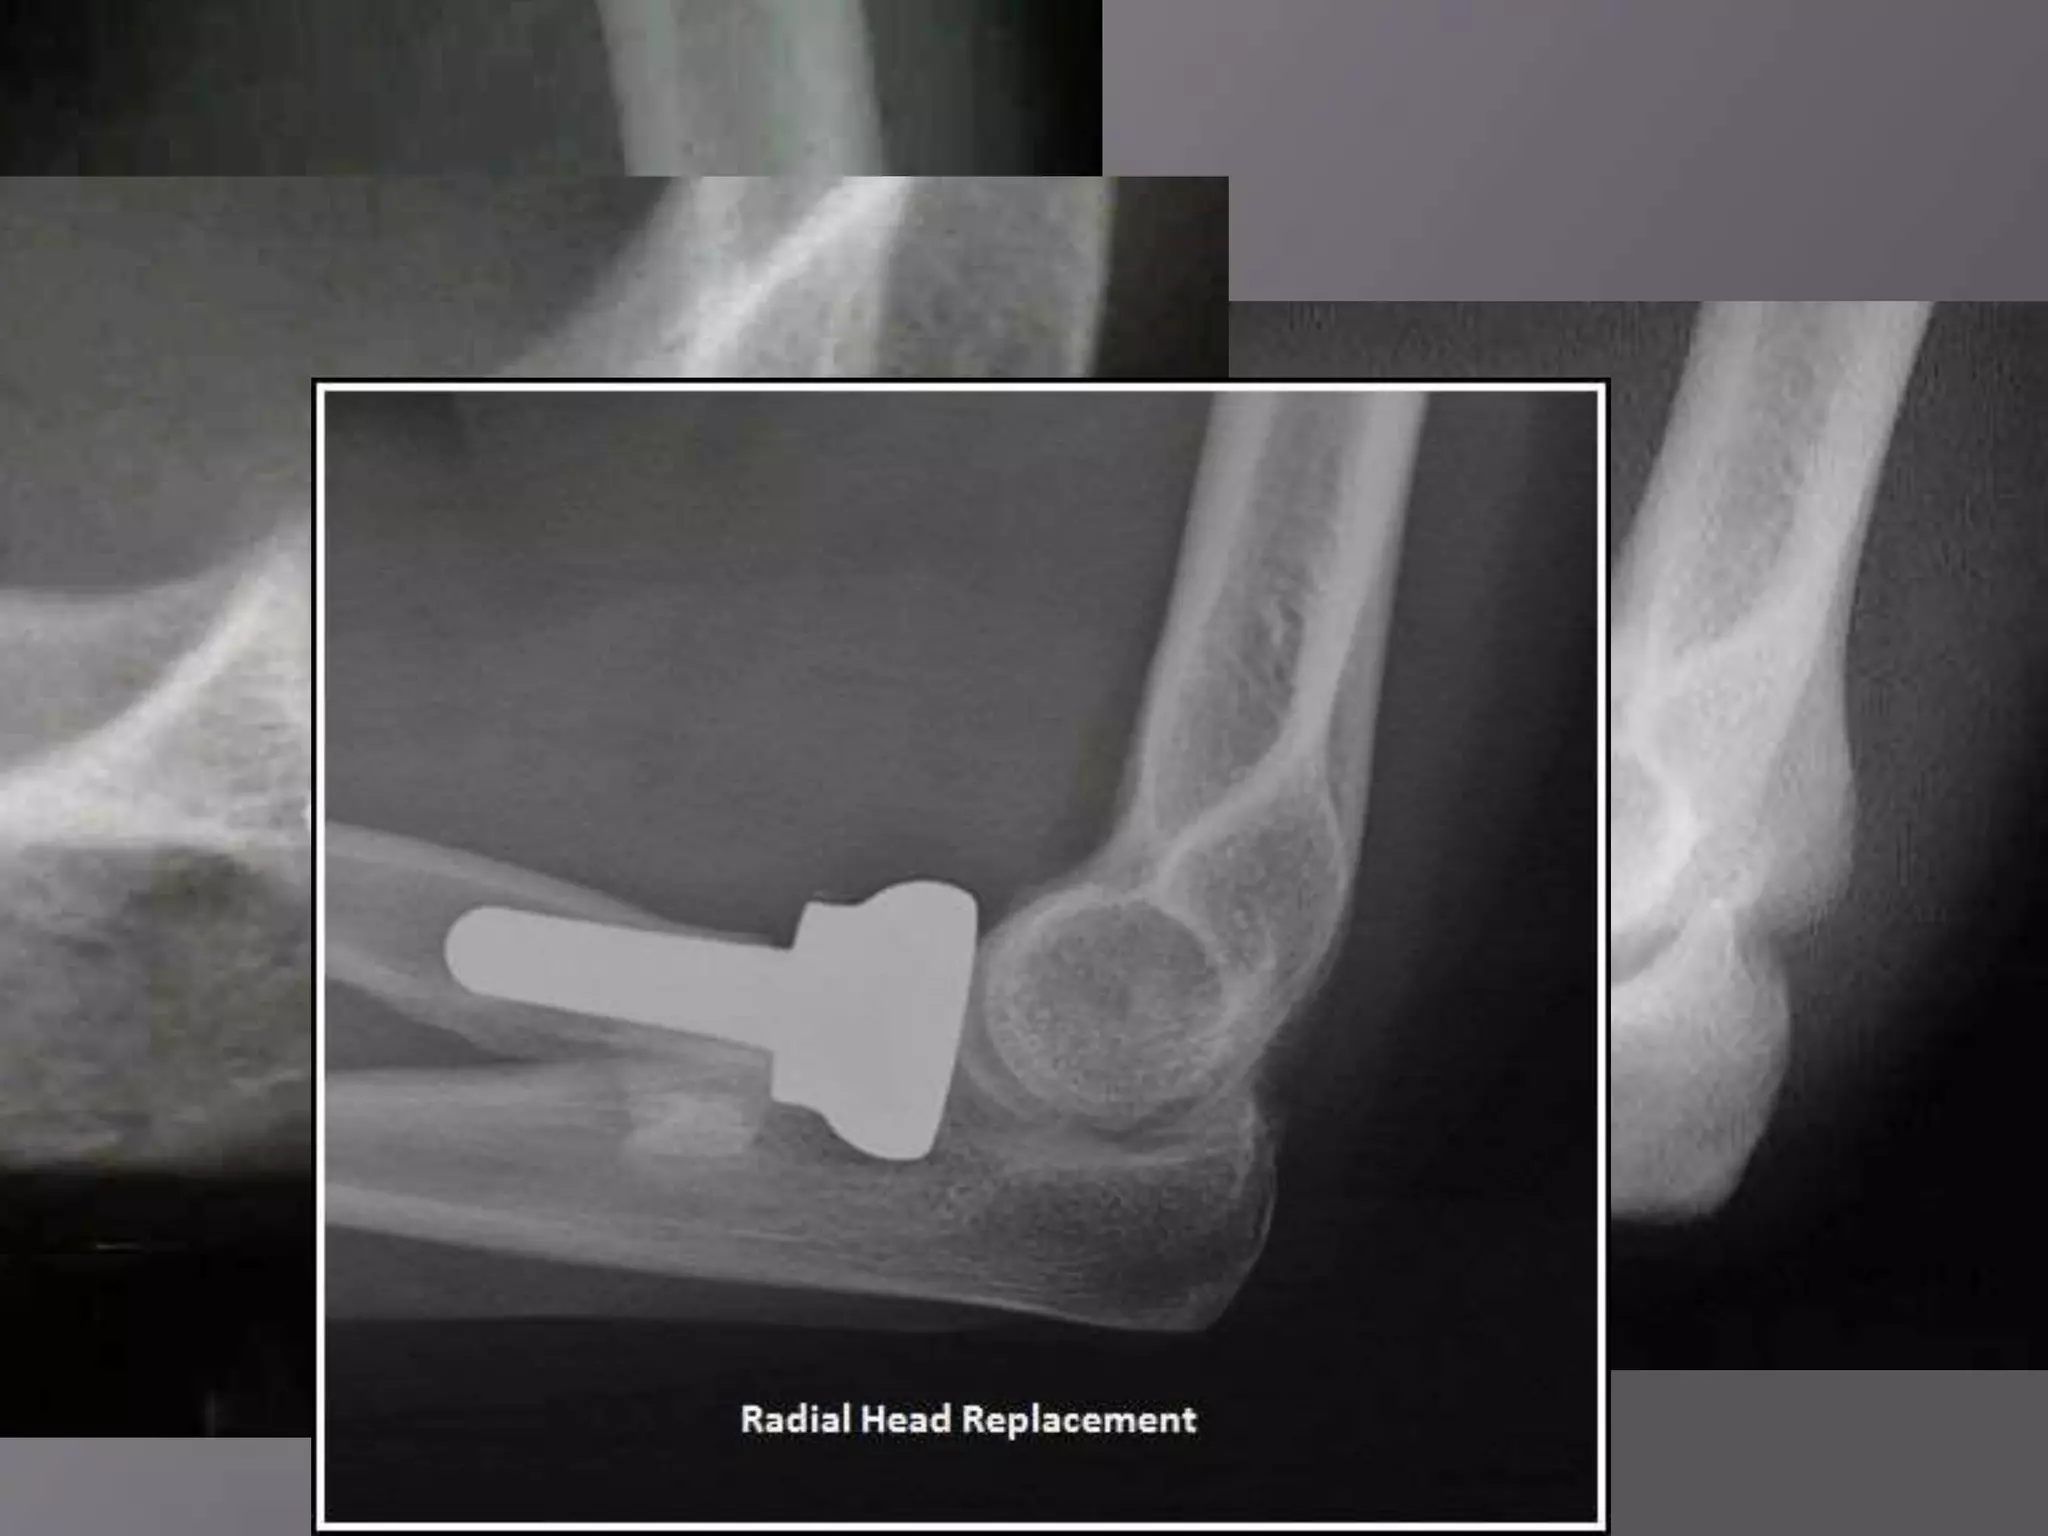

This document discusses the terrible triad injury of the elbow, which involves fractures of the radial head, coronoid process, and posterolateral dislocation. It notes the poor outcomes associated with this injury like stiffness, instability, and hardware failure. The document outlines the relevant anatomy of the medial collateral ligament and lateral uncular collateral ligament. It describes the mechanism of injury, known as the fall on an outstretched hand, and how the ligaments and capsule fail in this injury. Diagnostic imaging and classification of radial head and coronoid fractures are covered. Treatment options including observation, resection, open reduction internal fixation, and replacement are presented. Surgical approaches and techniques are also outlined.